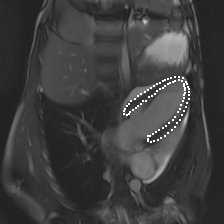

Accurate segmentation and motion estimation of myocardium have always been important in clinic field, which essentially contribute to the downstream diagnosis. However, existing methods cannot always guarantee the shape integrity for myocardium segmentation. In addition, motion estimation requires point correspondence on the myocardium region across different frames. In this paper, we propose a novel end-to-end deep statistic shape model to focus on myocardium segmentation with both shape integrity and boundary correspondence preserving. Specifically, myocardium shapes are represented by a fixed number of points, whose variations are extracted by Principal Component Analysis (PCA). Deep neural network is used to predict the transformation parameters (both affine and deformation), which are then used to warp the mean point cloud to the image domain. Furthermore, a differentiable rendering layer is introduced to incorporate mask supervision into the framework to learn more accurate point clouds. In this way, the proposed method is able to consistently produce anatomically reasonable segmentation mask without post processing. Additionally, the predicted point cloud guarantees boundary correspondence for sequential images, which contributes to the downstream tasks, such as the motion estimation of myocardium. We conduct several experiments to demonstrate the effectiveness of the proposed method on several benchmark datasets.